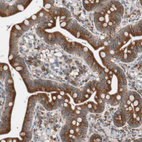

Immunohistochemical staining of human Prostate shows strong cytoplasmic positivity in glandular cells.